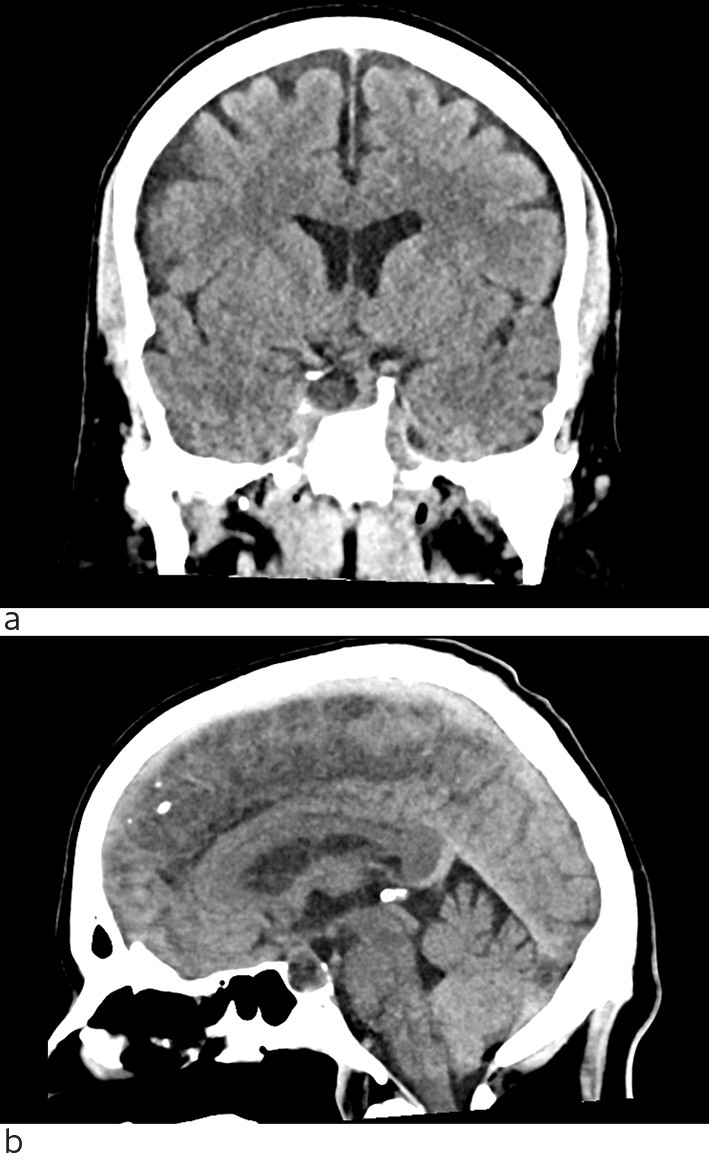

Ved regranskning så man at CT caput tatt ved innleggelsen viste en lavattenuerende lesjon i hypofysen (fig 2). MR caput tatt som øyeblikkelig hjelp-undersøkelse viste blødning i et hypofyseadenom med bukning inn i sinus cavernosus på høyre side og affeksjon av nervus abducens. Det var ekspansjon av sella turcica med manglende laterale høyre vegg og kraftig uttynning av bakre vegg, som var forenlig med et adenom som hadde utviklet seg over lang tid med remodellering av omliggende ben. Det var også noen uspesifikke lesjoner i hvit substans. Pasienten ble samme kveld overført til nevrokirurgisk avdeling ved universitetssykehus. Han ble operert neste dag med transsfenoidal reseksjon av hypofysetumor og blødning.

Denne kasuistikken understreker viktigheten av å utrede og observere pasienter med kraftig, akutt oppstått og vedvarende hodepine på en systematisk måte. Det kan være vanskelig å stille riktig diagnose. I vårt tilfelle tok det fem dager. Vi hadde slått oss til ro med utførte CT-undersøkelser hvor det var oversett forandringer i hypofysen. Da det tilkom begynnende diplopi tredje dagen, kunne man tenkt på patologi ved basis av hjernen. Først da det oppsto klinisk tydelig abducensparese og begynnende hyponatremi den fjerde dagen, ledet det tankene i retning av diagnosen. Tverrfaglig diskusjon mellom nevrolog, indremedisiner og radiolog var viktig.

En annen lærdom fra denne sykehistorien er at regranskning av tidligere utførte radiologiske undersøkelser i lys av ny klinisk informasjon kan føre til at man oppdager patologi som har blitt oversett.